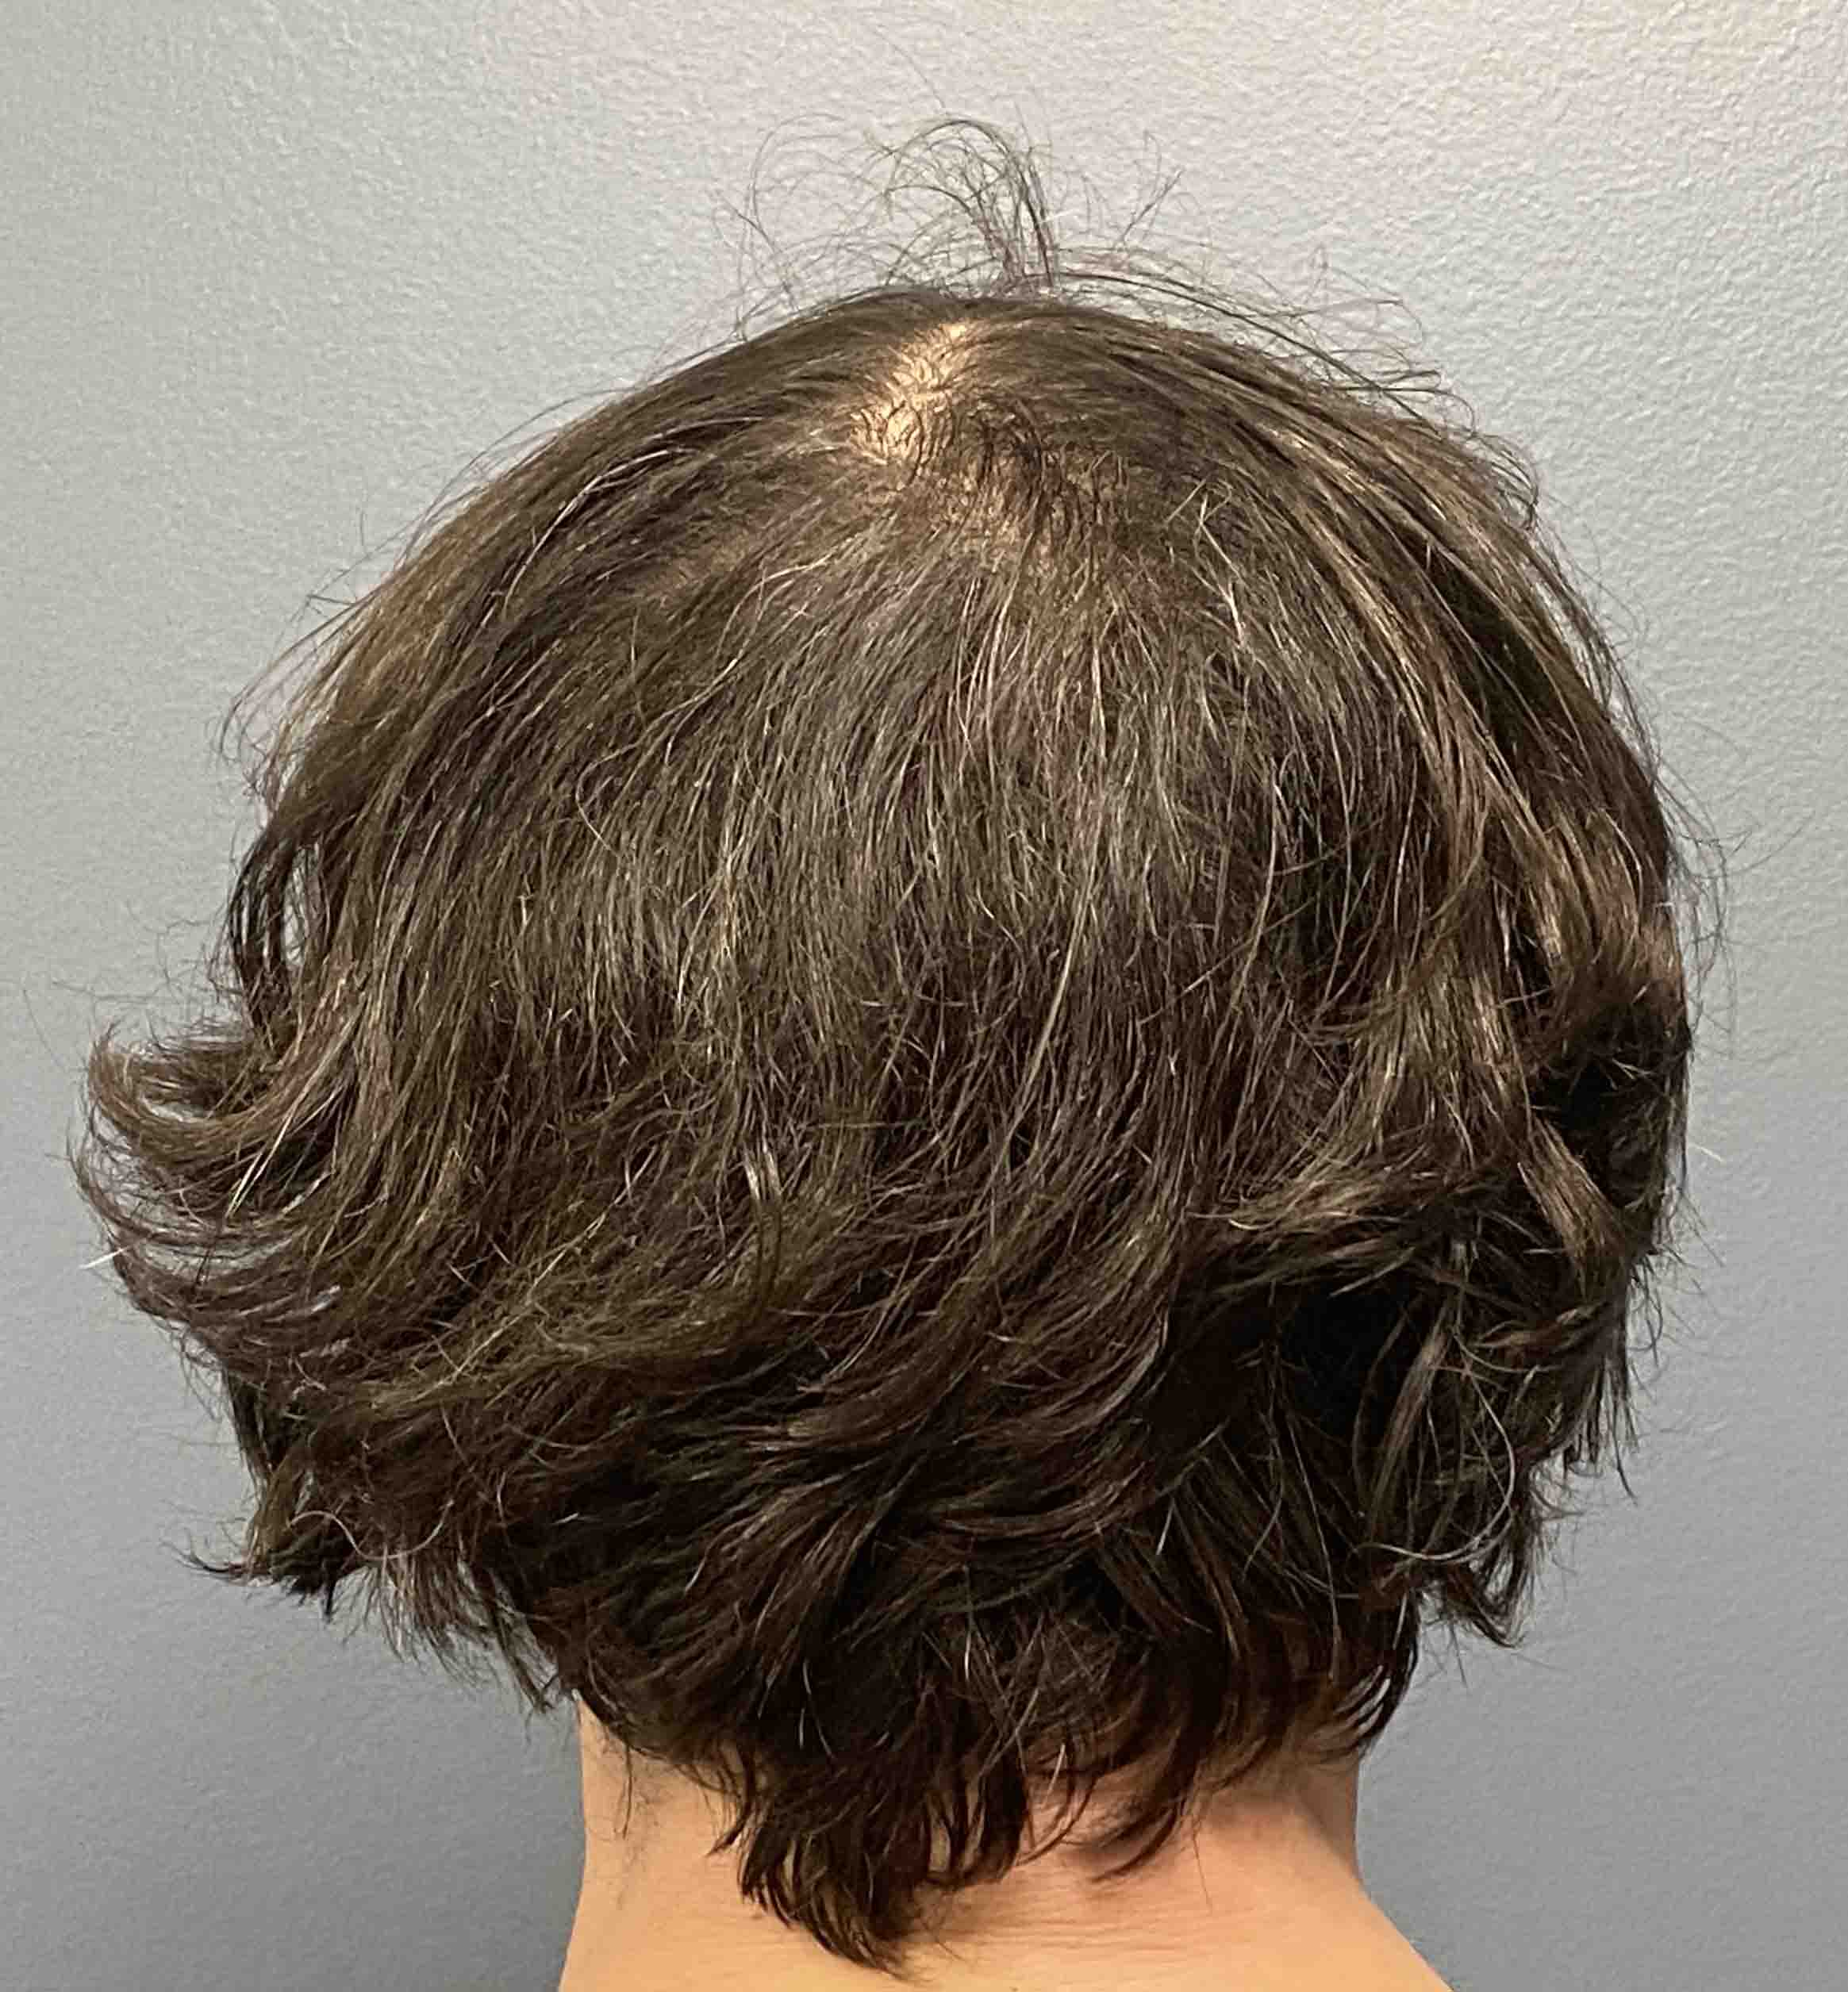

Desire for reduction of sagittal crest that became apparent over the with thinning of the hair.

Mid-sagittal crest skull prominence reduced through a limited scalp incision using high speed burring and large toothed rasps.

Desire for reduction of sagittal crest that became apparent over the with thinning of the hair.

Mid-sagittal crest skull prominence reduced through a limited scalp incision using high speed burring and large toothed rasps.